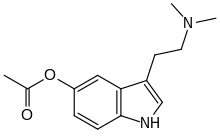

| 5-AcO-DMT | artificial | 5-OCOCH3 | CH3 | CH3 | 5-acetoxy-N,N-dimethyltryptamine | 16977-50-7 |